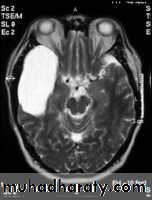

ARACHNOID CYST :

-clear csf filled cyst.

- occur due to congenital splitting of the arachnoid membrane.

- they are intracranial but extracerebral.

-cam be seen in middle ,posterior cranial fossa , suprasellar region & behind the 3rd ventricle.

- they can be large enough to produce mass effect or obstructive hydrocephalus.

- there may be Hypoplasia of underlying cerebral tissue such as the temporal pole.

Axial T2-weighted MRI image through the midbrain, showing a right middle cranial fossa homogeneous lesion) with CSF signal intensity and no perceptible wall or internal complexity. There is associated remodeling of the adjacent sphenoid bone and brain displacement..